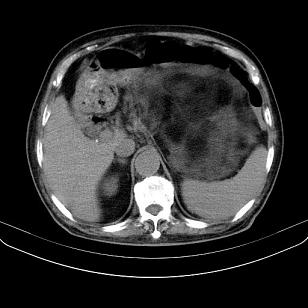

标题: CT21671:男,88岁,左上腹包块 [打印本页]

标题: CT21671:男,88岁,左上腹包块

患者因咳嗽而住院,自觉右上腹包块,无其他不适。

脂肪肉瘤,应测ct值。

另肠腔扩张及液平,肠梗阻?

考虑腹膜后脂肪肉瘤可能性大。 畸胎瘤不除外。